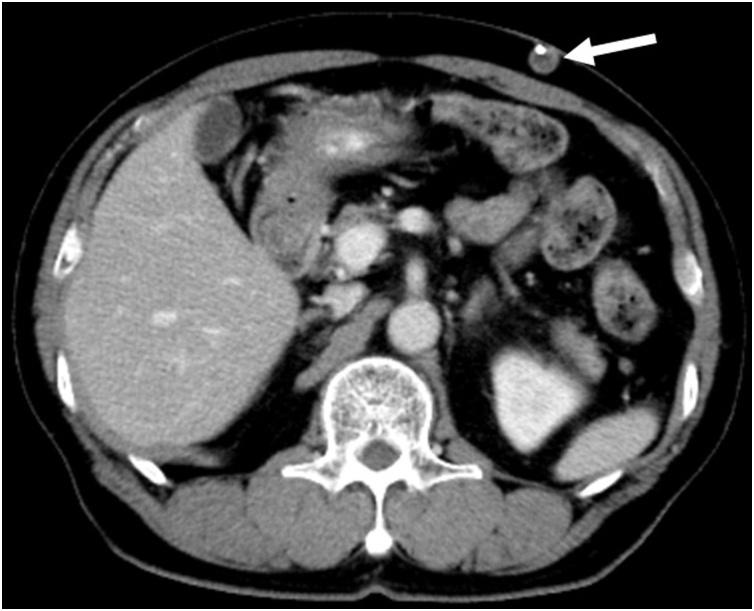

A 79-year-old man who had a VP shunt for hydrocephalus two years earlier underwent laparoscopic right colectomy for ascending colon cancer. Six months after the colectomy, imaging examinations showed mass formation in the subcutaneous tissue of the abdominal wall along the VP shunt. Because of the possible metastasis of colorectal cancer and the fact that it was a solitary lesion, a tumor resection with replacement of the VP shunt was performed. Histopathological examination revealed that the mass was a metastasis of colon cancer.

一名79岁男性,两年前因脑积水置入VP分流管,此次因升结肠癌接受腹腔镜右半结肠切除术。结肠切除术后六个月,影像学检查显示沿VP分流管的腹壁皮下组织有肿块形成。鉴于结直肠癌可能发生转移且为孤立性病变,遂行肿瘤切除并更换VP分流管。组织病理学检查显示该肿块为结肠癌转移灶。